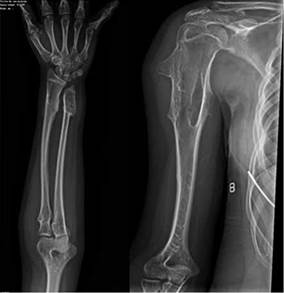

Fuente: Cortesía del Dr. Ledezma, CEMED.

Figura 2:

(A) Proyección AP de antebrazo izquierdo muestra osteocondromas sésiles en las 1ra, 2da, 3ra y 4ta falanges proximales. Exostosis sésil en extremo proximal y exostosis pediculada en extremo distal del radio. Luxación de la articulación radio-cubital distal.

Lesión lítica expansiva en cabeza de cubito que desplaza los tejidos blandos suprayacentes acompañado de acortamiento longitudinal del mismo. Ligera angulación dorsal de la diáfisis del radio y cubito, incremento del espacio interóseo y configuración triangular de la primera hilera de los huesos del carpo (Sugerente de deformidad de Madelung).

(B) En proyección AP de brazo derecho se evidencia osteocondroma sésil en extremo proximal de húmero que desplaza los tejidos blandos suprayacentes (sin observarse reacción perióstica), que al examen físico del paciente se evidenciaba como un bulto palpable e indoloro en extremo superior de brazo derecho.